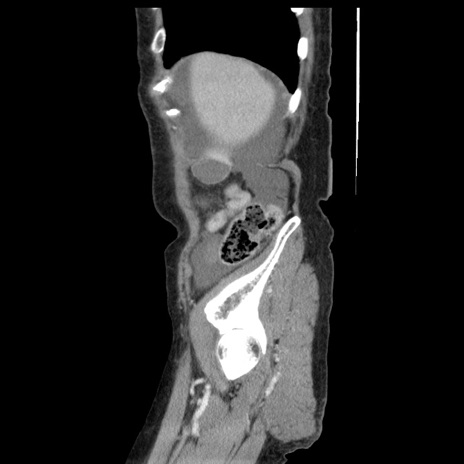

症例1(矢状断像)

【症例】80歳代女性

【主訴】腹痛

【現病歴】8時間前から腹痛あり来院。

【既往歴】糖尿病、脂質異常症、子宮体癌にて子宮全摘術

【身体所見】意識清明・会話良好だが腹痛で苦悶様、全腹部にわたって反跳痛と圧痛あり

【データ】WBC 13600、CRP 0.14、LDH 224、CK 90